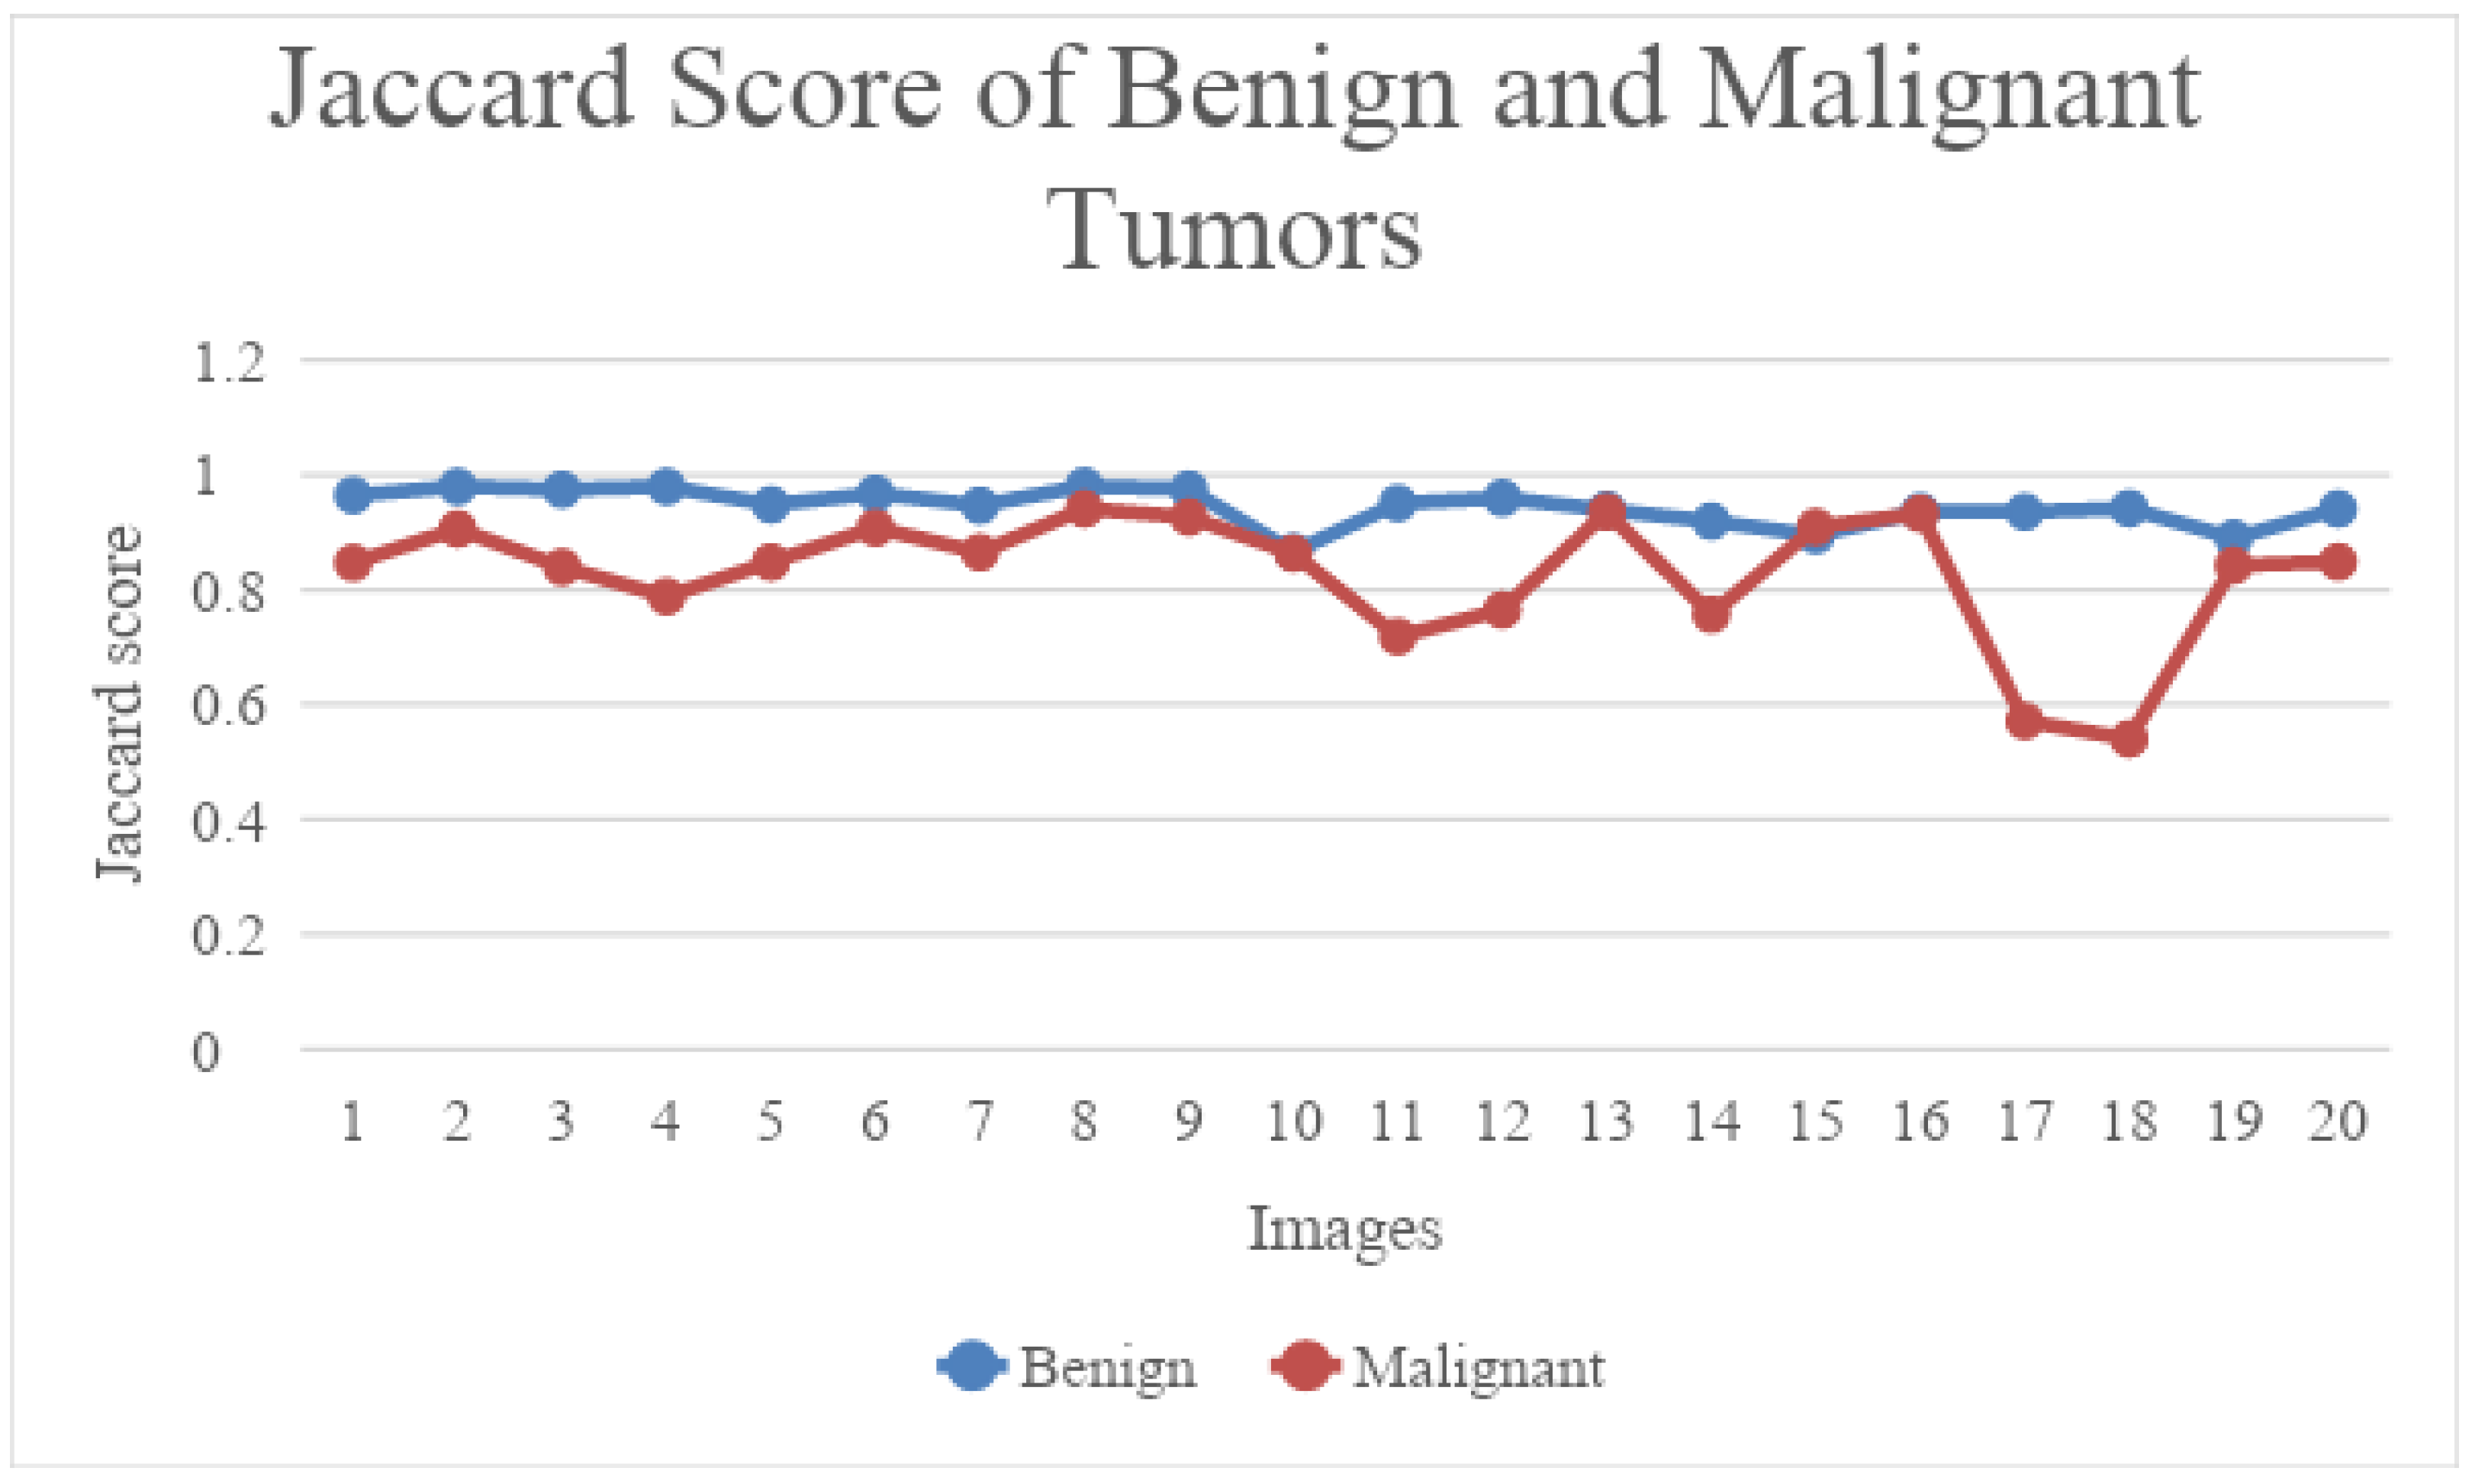

4.2. Segmentation Results Using the UNet Model